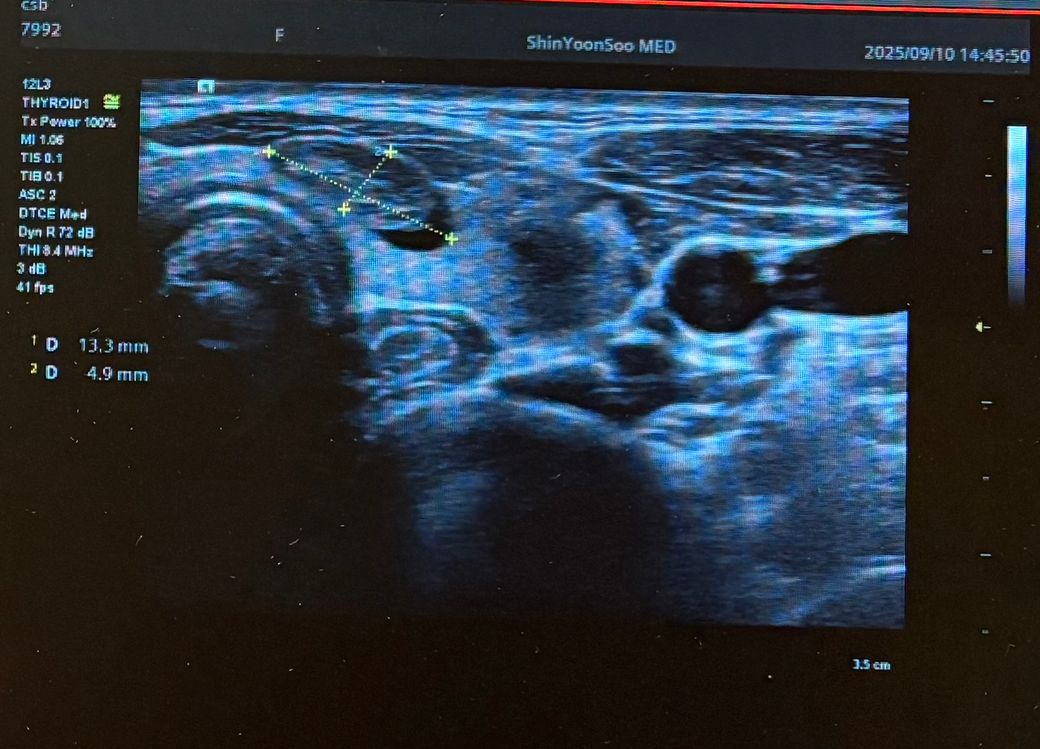

최근 동네 의원에서 갑상선초음파를 보다가 왼쪽 갑상선에 큰 혹 한개와 작은혹 한개가 발견되어 조직검사가 필요할것 같다고 의뢰서를 써주셔서 상급병원으로 예약잡고 저번주에 초진 봤습니다.

Lt 1ower lobe

1.88x1.4x2.84cm mixed nodule Lt middle lobe 1.22x0.37x 0. 49cm의 nodule 소견으로(의뢰서에 적혀있던 내용) 초진 보러가니 초음파 사진만 보시고는 식도와 신경에 들러붙어있고 점점점 커지면서 추후엔 응급수술로 진행될 수 있으니 아직 젊을때 빠르게 수술로 떼어내자고 결론은 수술밖에 없다고 냅다 수술일정 한달뒤로 잡고왔습니다.

왼쪽에 약 3cm가량으로 전체가 혹일거라며 상황이 많이 안좋은거고 위치가 안좋다고 하셔서 다음주에 수술전 검사 받은 후 2주뒤 입원으로 일정이 잡혔는데 보통 세침검사 또는 총생검사 후 수술 여부가 결정되는걸로 알고있는데 ..

• 2번 째 사진